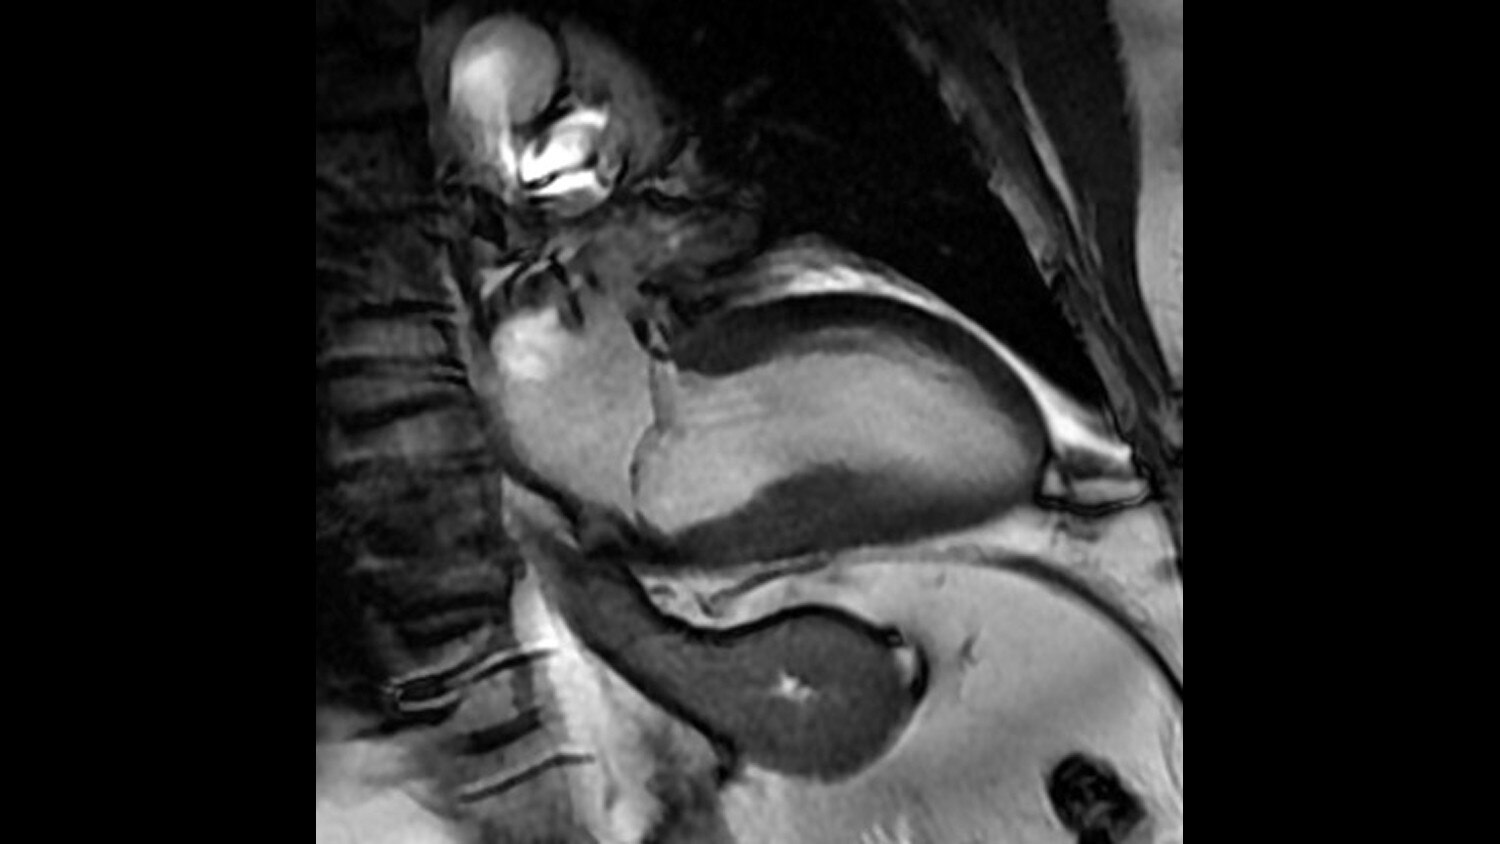

A large usable field of view is needed to properly image off-center anatomy such as a shoulder or hip. So the Discovery* MR750w features a 70 cm flared, open bore design with a large 50 x 50 x 50 cm field of view.

GEM Posterior Array - Embedded high-density posterior array with optimal coil element geometry that enhances spine, abdomen, cardiac, and lower extremity scanning.

GEM Peripheral/Vascular Array - A high-density PV / lower extremity array that facilitates imaging of the thighs and lower legs with parallel imaging in all 3 planes. The coil incorporates an innovative self-supporting hinge design between the upper and lower elements to accommodate patients of various sizes with simplified set-up.